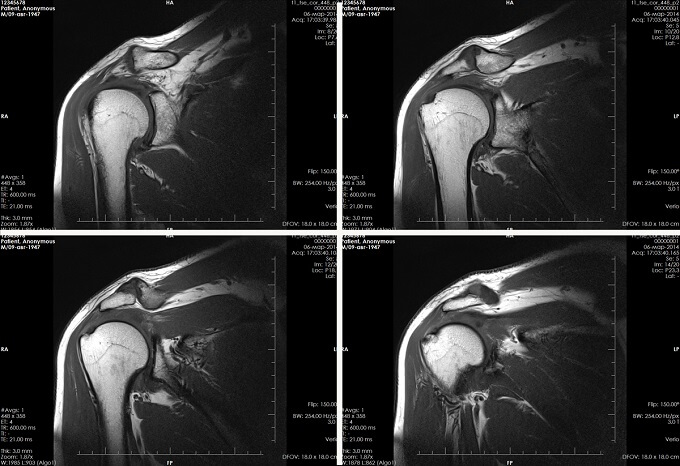

При сомнениях в постановке диагноза пациента отправляют на дополнительное аппаратное обследование: МРТ и КТ, рентген. Эти методики помогут подтвердить предварительный диагноз, найти причину заболевания.

Защемление нерва в плечевом суставе диагностируется методами:

- физикального обследования неврологом;

- рентгенографии;

- томографии (МРТ либо ПЭТ―КТ);

- лабораторных исследований крови, урины, синовиальной жидкости.